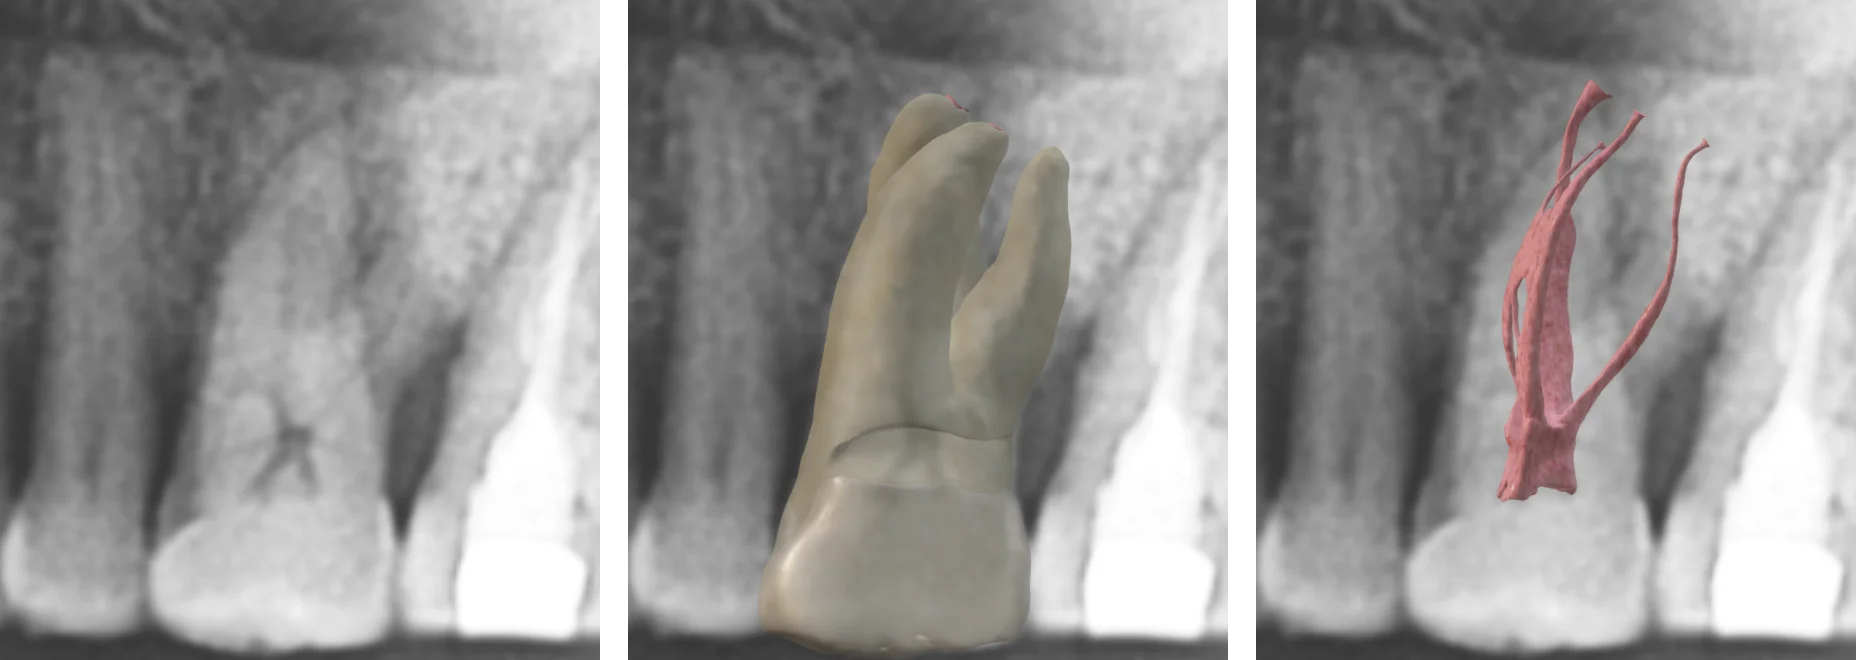

🎯 Finding the Hidden Palatal Root

Palatal roots are often tricky to locate, but now that we have a real 3D model as a reference, spotting its shape and positioning becomes much easier.

Tracing hidden palatal root

Now, let’s train our eyes to detect these subtle shadows in future cases. By practicing with actual 3D models overlaid onto X-rays, we can improve our ability to mentally reconstruct the tooth’s spatial anatomy.